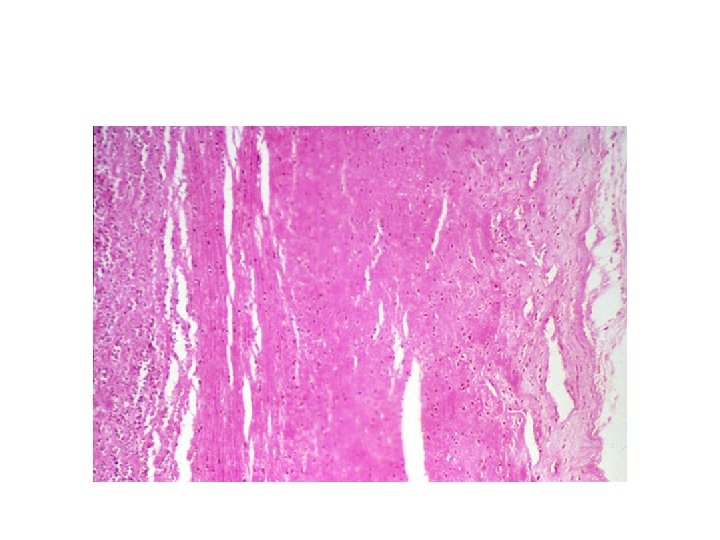

ULCERATION • LOCAL DEFECT CAUSED BY SLOUGHING OF NECROTIC TISSUE.

GASTRIC ULCER